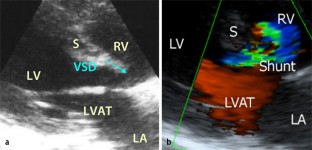

Schwangere mit angeborenem, komplexem zyanotischen Herzfehler haben ein hohes Morbiditäts- und Mortalitätsrisiko. Die Frage, ob ein regionalanästhesiologisches Verfahren Vorteile gegenüber allgemeinanästhesiologischen Verfahren bietet, kann aus der Literatur nicht eindeutig beantwortet werden. Es wird über eine 37-jährige I. Gravida mit teilweise korrigiertem, komplexem zyanotischen Herzfehler mit Pulmonalklappenatresie und einem Ventrikelseptumdefekt berichtet. Die Patientin wurde in der 31. SSW per Sectio in Regionalanästhesie entbunden. Für die Sectio erhielt sie ein invasives Monitoring, bestehend aus einer arteriellen und zentralvenösen Druckmessung und einem lumbalen Periduralkatheter (PDK). Die Sectio wurde ohne Komplikationen durchgeführt. Das interdisziplinäre Management ermöglichte die erfolgreiche Versorgung bei dieser kardialen Hochrisikoschwangerschaft. Für die Sectio bei einer kardialen Hochrisikoschwangeren scheint ein regionalanästhesiologisches Vorgehen trotz gegenteiliger Aussagen in der Literatur möglich zu sein.

A 37-year-old gravida I with cyanotic heart disease presented for caesarean section in the 31st week of gestation. Caesarean section was performed uneventfully with the patient under epidural anaesthesia accompanied by invasive monitoring. Postoperative echocardiography showed no change in the shunt fraction, volumes or the ventricular function. Every patient with complex comorbidities has to be managed according to individual prerequisites and the experiences and preferences of the team. For such high risk pregnancies regional anaesthesia seems to be a possible option although no clear evidence can be found in the literature.